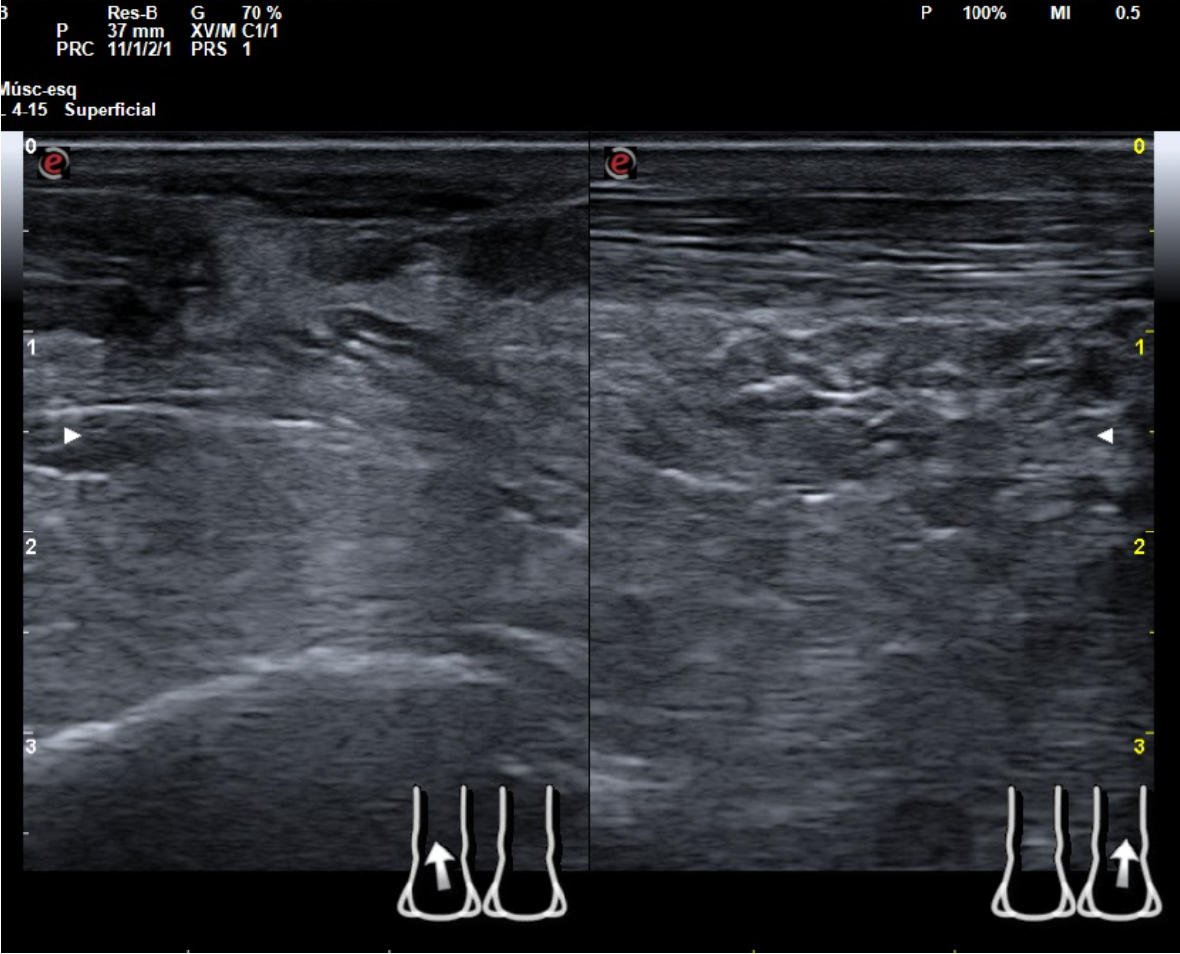

Hallazgos ecográficos

En tendón aquíleo izquierdo se aprecia rotura completa con solución de continuidad de 2 cm localizada a 5,7 cm de su inserción en el calcáneo. Presenta áreas hipoecoicas peritendón que sugieren hematoma secundario. En el aquíleo derecho presenta leve hipoecogenicidad y engrosamiento del tendón sin solución de continuidad que sugiere tendinosis. Importante componente inflamatorio. No datos de TVP. Poplítea y safena externa permeables y compresibles en ambas extremiedades.

Juicio clínico: Rotura completa de tendón de Aquiles izquierdo. Tendinosis aquílea derecha.

Diagnóstico diferencial: esguince de tobillo, artritis.